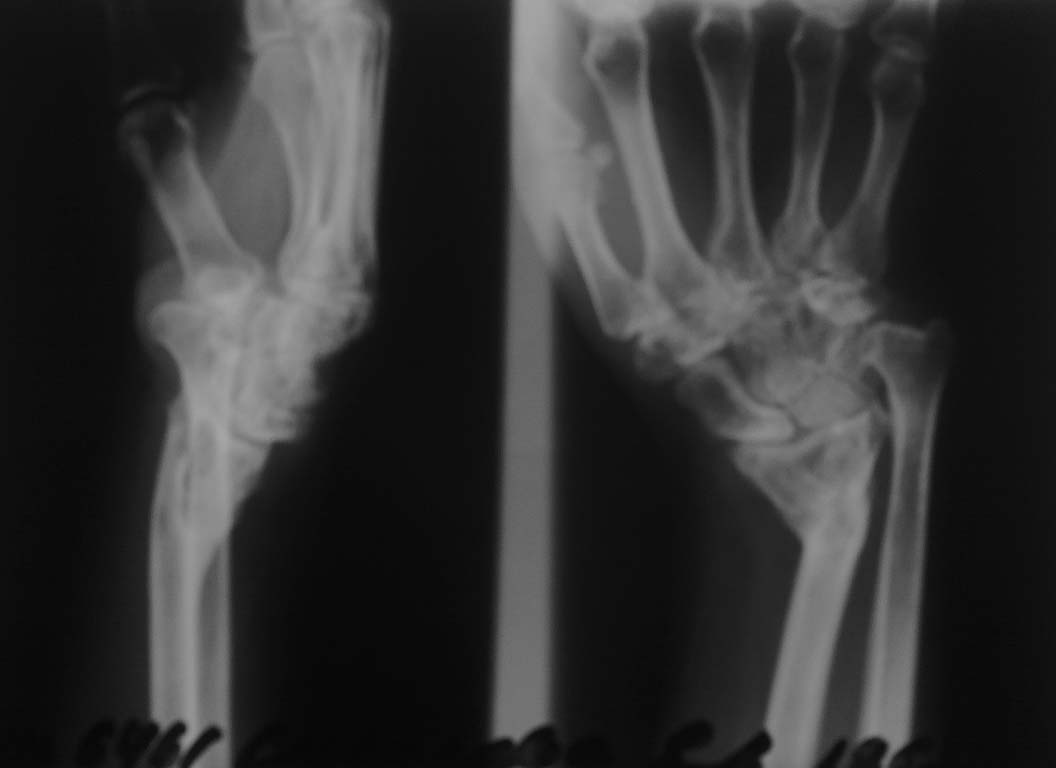

Неправильно сросшийся перелом лучевой кости

Добрый День. К нам обратилась женщина, 47 лет, с деформацией области лучезапястного сустава. Из анамнеза - травма 9 лет назад.

Амбулаторное лечение. В настоящее время - имеется деформация н\3 предплечья, движения в лучезапястном суставе минимальные. Женщина по професии - повар. Желает восстановить функцию конечности.Планируем:1 этап - остеотомия лучевой кости и наложение спицевого аппарата2 этап - остеосинтез пластиной с костной пластикой

А что с подвижностью пальцев и в локтевом суставе? Есть ли боли? По представленным снимкам сложно оценить состояние костей запястья.

А как на счёт функции локтевого сустава? Ответа на этот вопрос не было. Дело в том, что это деформация Маделунга и часто бывает при замыкании зоны роста лучевой кости, чаще в результате травмы. А в нашем случае говорить о замыкании зоны роста лучевой кости говорить не приходится, но судя по снимкам укорочение луча приличное. Нет ли тут вывиха головки луча? Неплохо было бы сделать снимки локтевого сустава. А на счёт тактики лечения - нужно восстановить длину лучевой кости - остеотомией с наложением ЧКДО по Илизарову с последующим удлинением и исправлением деформации.